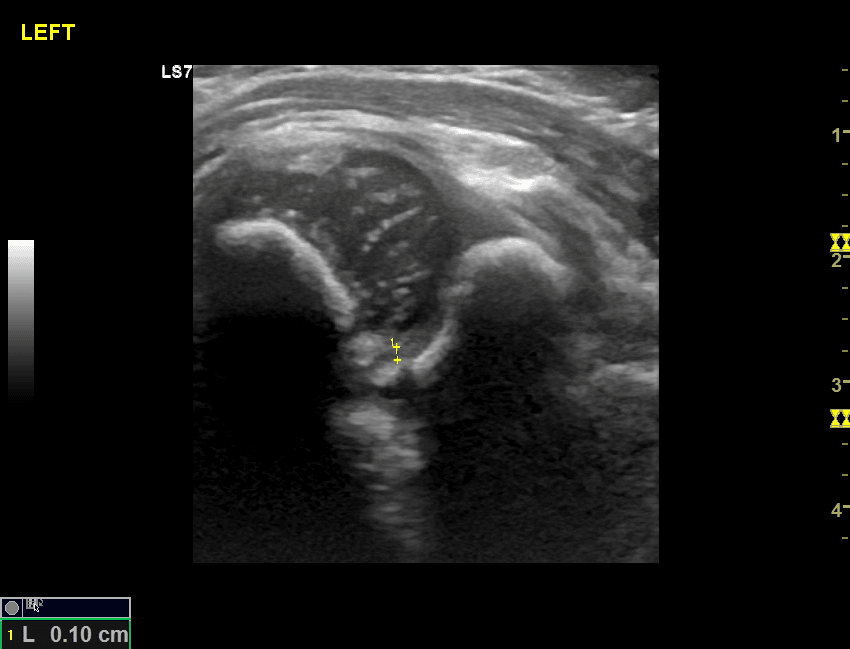

To 1992 H Rosendahl πρότεινε το συνδυασμό των 2 επικρατέστερων μεθόδων ( μέθοδος Graf και μέθοδος Harcke )τη γνωστή σήμερα μέθοδο Rosendahl ή αλλιώς τροποποιημένη μέθοδος Graf( (modified -Graf method) η οποία από το 2011 με βάση τις κατευθυντήριες οδηγίες της Ευρωπαϊκής Παιδοακτινολογικής Εταιρίας (ESPR) είναι η προτεινόμενη μέθοδος εξέτασης. Η Rosendahl και ο Graf είναι πολύ αυστηροί στην μεθοδολογία της εξέτασης και ιδιαίτερα στη σωστή λήψη των υπερηχογραφικών εικόνων ώστε να αποφευχθούν τυχόν λάθη. Η μέτρηση των γωνιών κατά Graf προϋποθέτει να περιλαμβάνονται στην εικόνα όλα τα ανατομικά στοιχεία της άρθρωσης και οι 3 γραμμές να διέρχονται με ακρίβεια από τα σωστά σημεία.

Έτσι μόνο στην τέλεια άρθρωση οι 3 γραμμές εφάπτονται στο ίδιο σημείο, εύρημα όχι συχνό και όχι υποχρεωτικά αναμενόμενο στη φυσιολογική άρθρωση !! Αντίστοιχα η δυναμική εξέταση χρήζει ιδιαίτερης προσοχής για να αποφευχθούν τυχόν λάθη και να μην «ταλαιπωρείται» το βρέφος με συχνές –άσκοπες επαναλήψεις.